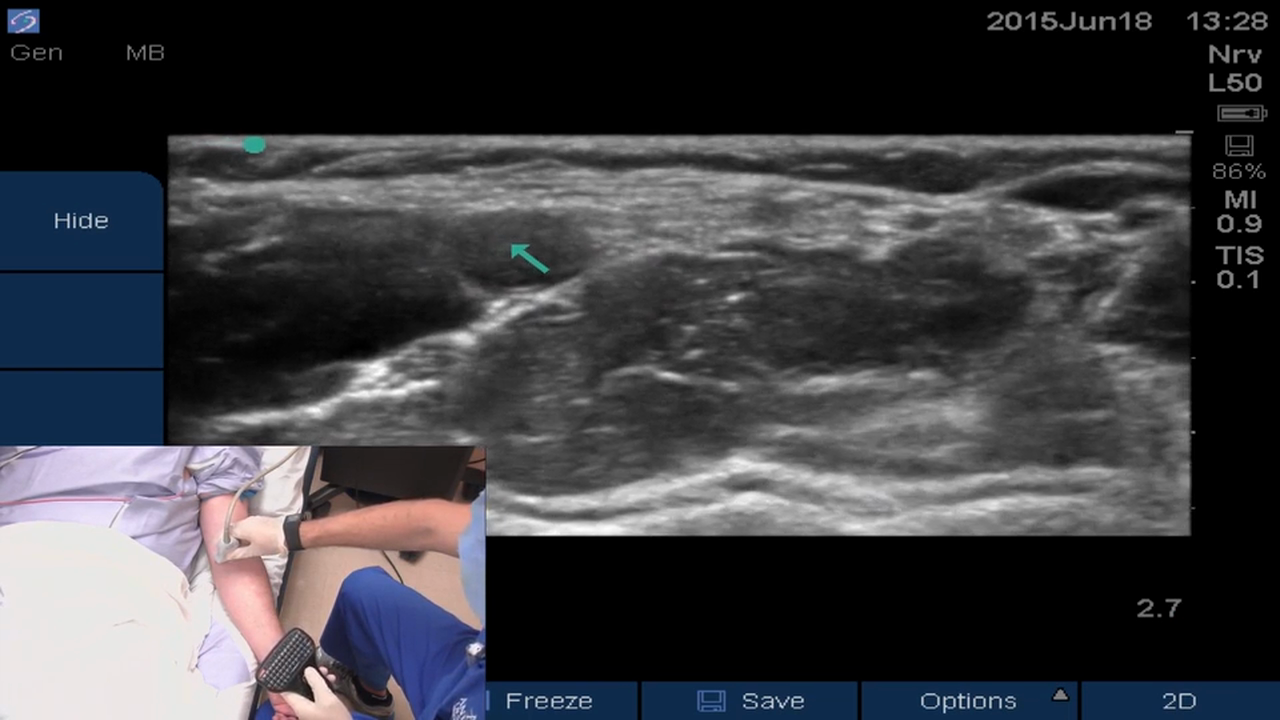

• Ultrasound-guided Peripheral IV Placement

Brandon Winchester demonstrates the placement of an ultrasound guided peripheral IV at the antecubital fossa using a long-axis in-plane technique.